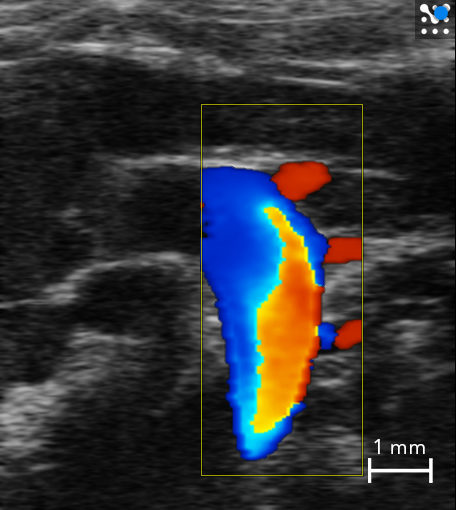

PW Doppler / Color Mode

Using Color Doppler Mode, flow velocities within vessels are color-coded. The intensity of the color is a function of velocity. Flow towards and away from the transducer is indicated either as red or blue, respectively.

Color Doppler - Renal vein/artery